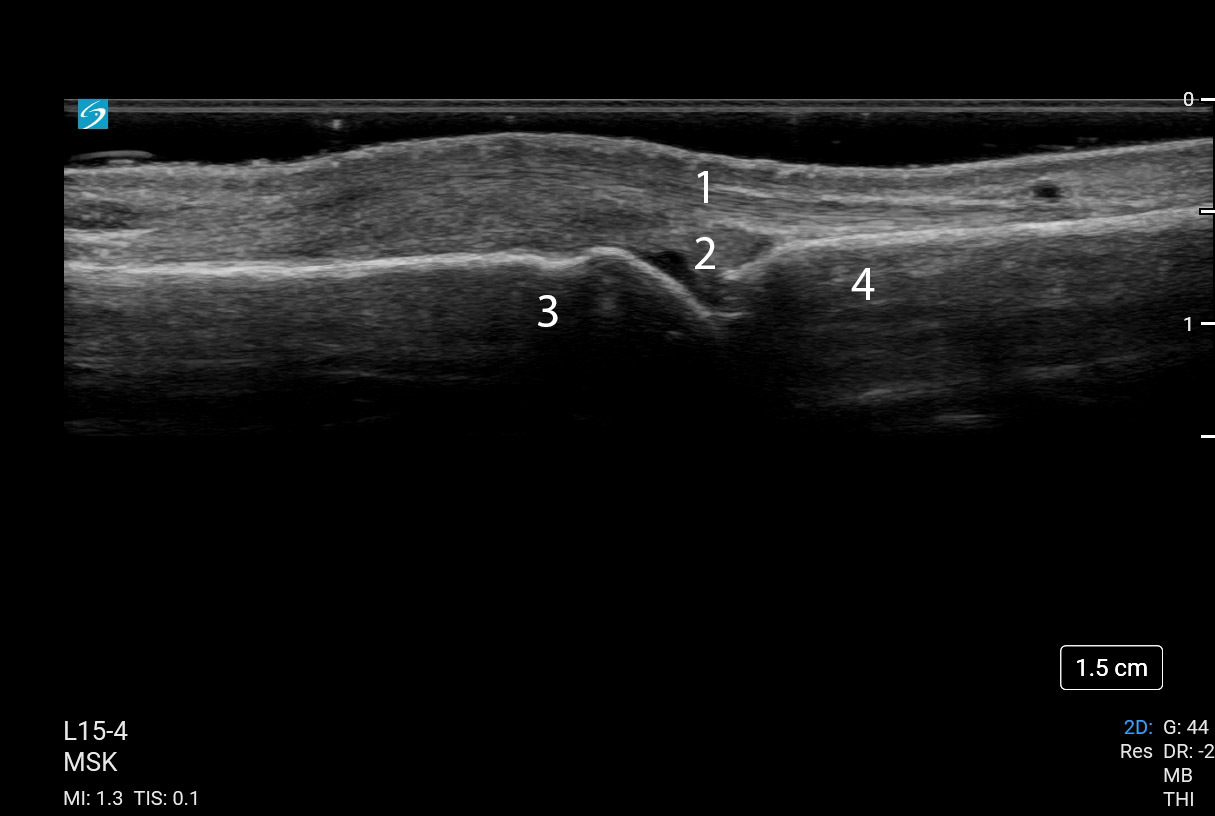

手部第 2 MCP 关节长轴图像

伸肌腱

脂肪垫

远端掌骨

近端趾骨